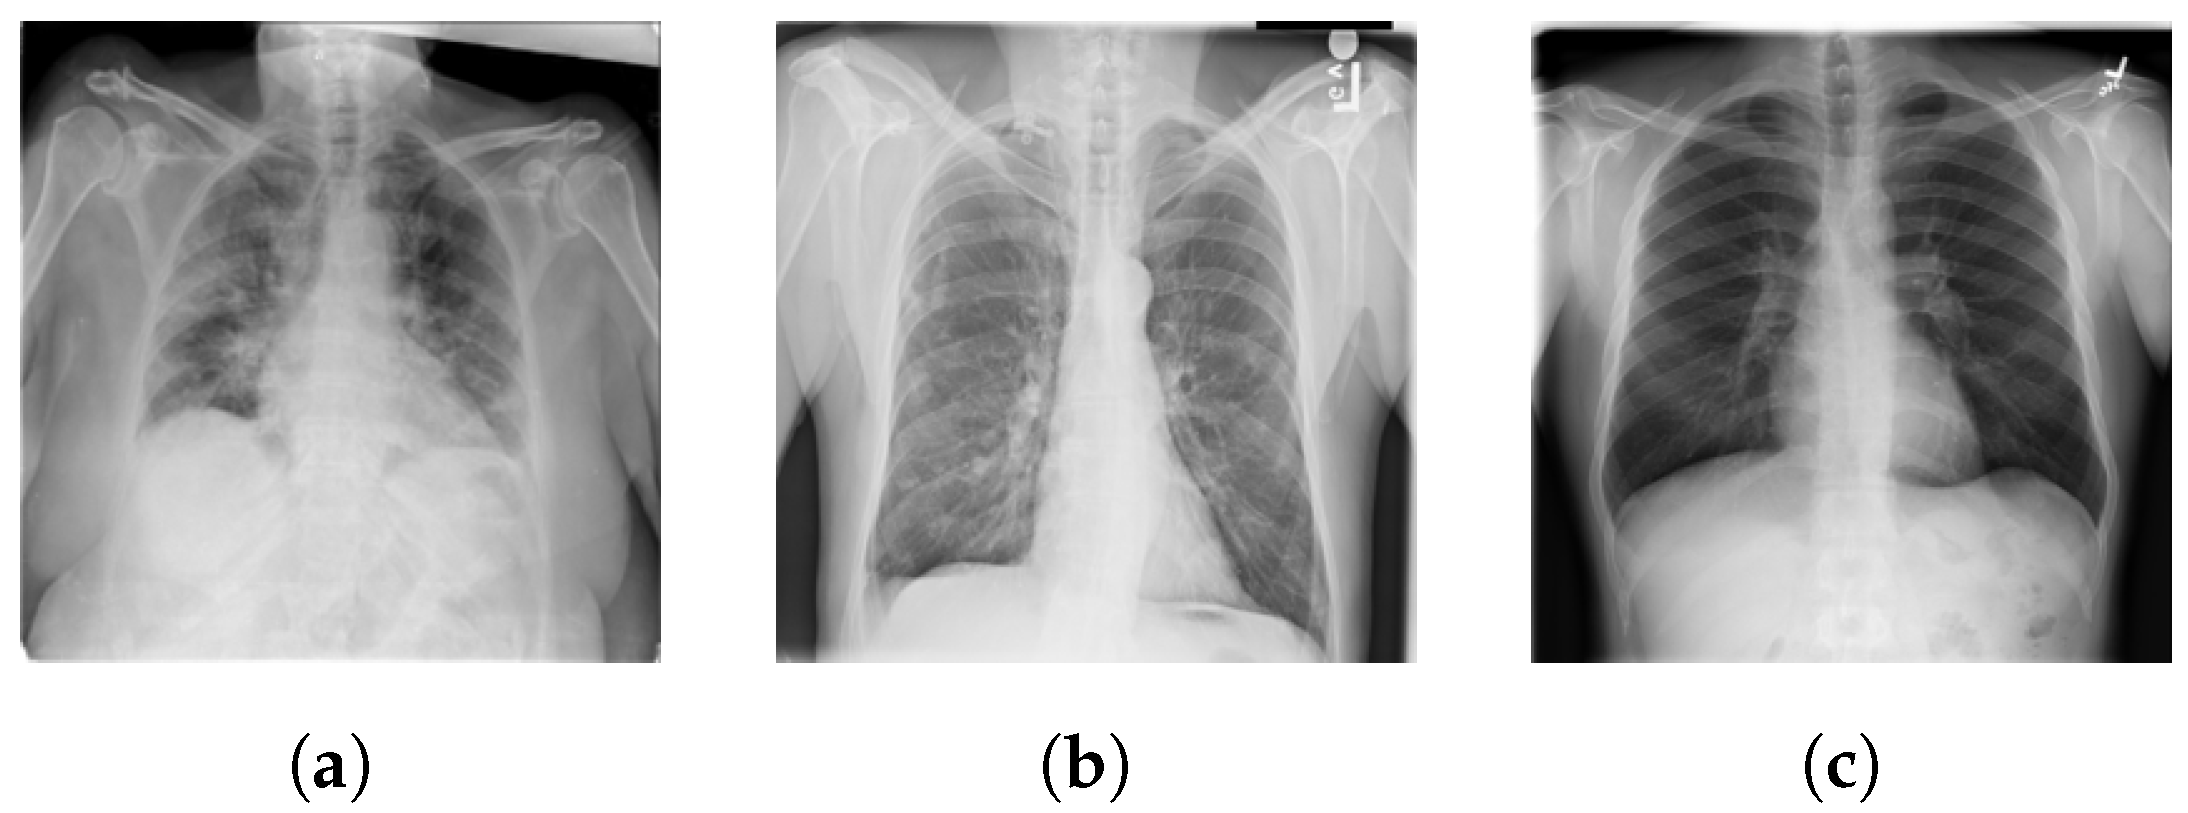

4.1. Dataset

5.1. COVID-19 Dataset